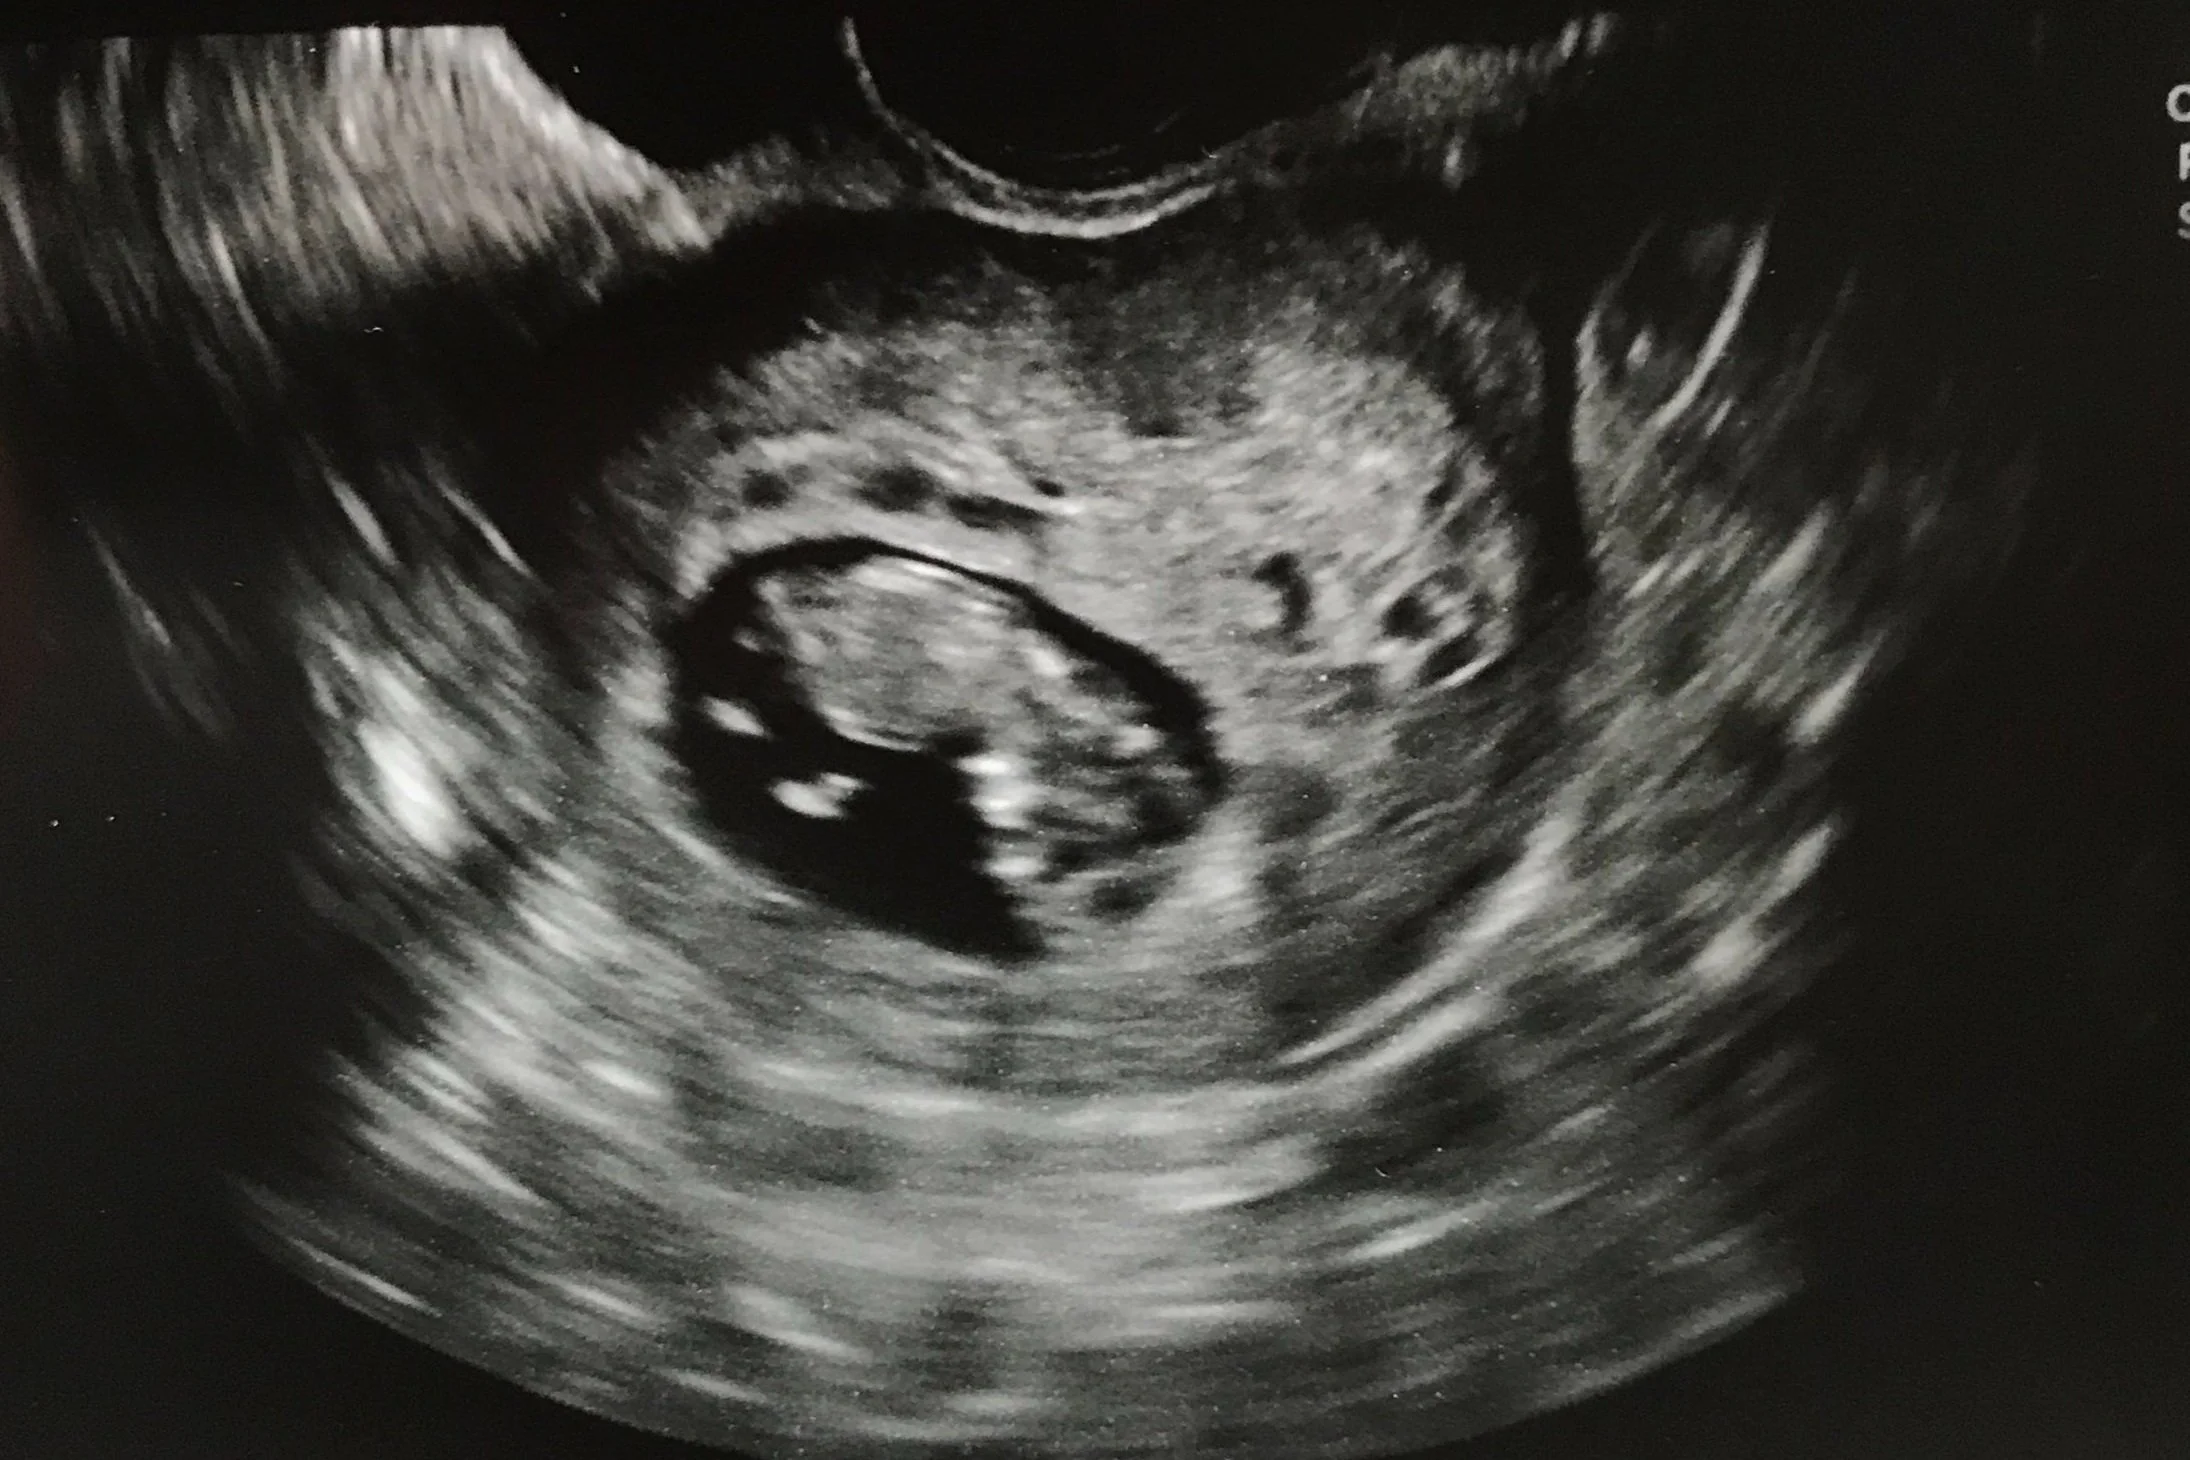

And then—finally, a sticky embryo!